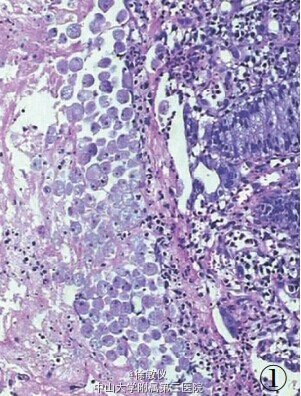

20岁男性,反复腹泻半年,加重2周伴少量脓血。 体检:肝、脾肋下未触及,全腹无压痛,无包块,无肌紧张,肠 鸣音正常,双下肢不肿。实验室检查:大便隐血(+);大便培养 +药敏:未培养出病菌;余均正常。肠镜:距肛缘10cm 以下直肠黏膜充血,水肿,散在多发浅溃疡。取直肠组织活检病理示:直肠黏膜固有层充血、水肿,伴淋巴细胞、浆细胞、中性粒细胞以及嗜酸性粒细胞等急慢性炎细胞浸润,并见淋巴滤泡形成,部分腺体杯状细胞减少,局部表面上皮脱落,糜烂面附有炎性渗出物及成片的大滋养体,滋养体内见一大核仁,胞质内有吞噬红细胞现象。病理诊断:直肠阿米巴病。患者住院8天,给予甲硝唑、大蒜素等药物抗阿米巴治疗后痊愈出院,痊愈后1年,随访无复发。